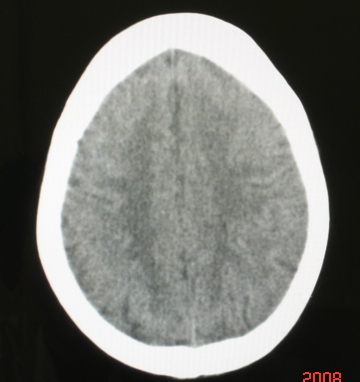

标题: CT13027:左顶叶低密度灶请大家指点 [打印本页]

标题: CT13027:左顶叶低密度灶请大家指点

病人女性,58岁.左颞部外伤2小时,自觉头痛头晕.否认其它疾病史.

病灶ct值28~31hu.